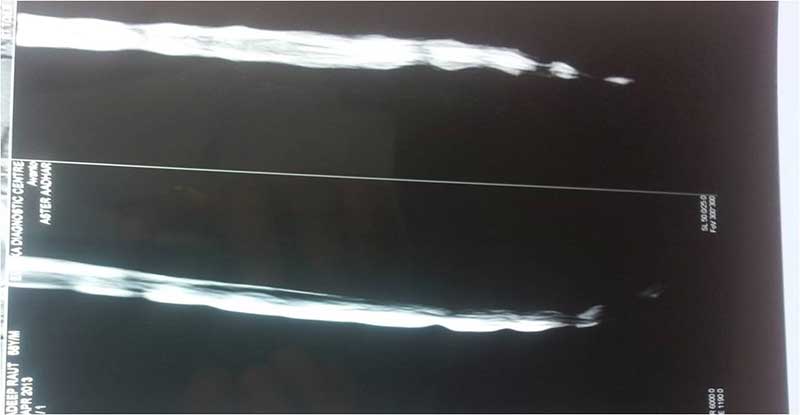

SEQ DISC 3